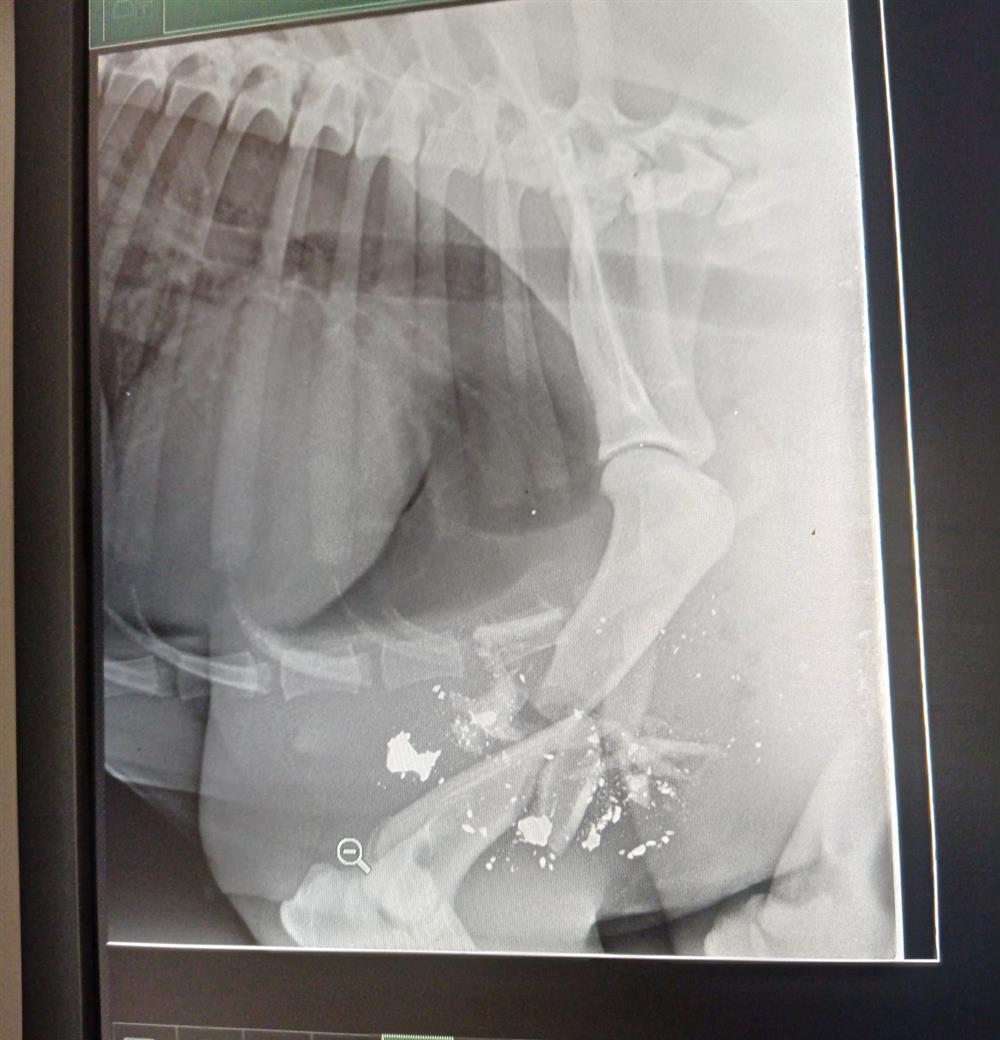

Όπως αναφέρει ο Περιβαλλοντικός Σύνδεσμος Δήμων περιοχής Αθήνας - Πειραιά, πρόκειται για θηλυκό ζώο, μέσης ηλικίας που έφερε βαρύ και διαμπερές τραύμα στο μπροστινό μέρος του σώματος του, ενώ όπως διαπιστώθηκε το βλήμα του είχε προκαλέσει συντριπτικό κάταγμα βραχιονίου, με διάσπαρτα θραύσματα του βλήματος (όχι σκάγια) να παραμένουν ενσφηνωμένα στα οστά.

Αφού για τρεις ημέρες καταβλήθηκαν προσπάθειες με οροθεραπεία, αναλγητική και αντιβιοτική αγωγή και τοπικές πλύσεις, εκτιμώντας όλη την εικόνα του τρομακτικού τραύματος και τον κίνδυνο ζωής που διέτρεχε το ζώο, οι γιατροί του ΔΙΚΕΠΑΖ ακρωτηρίασαν το μπροστινό αριστερό άκρο του και προχώρησαν σε διακοπή της εγκυμοσύνης με ωοθηκυστερεκτομή.

Οι γιατροί του ΔΙΚΕΠΑΖ δεν μπορούν να γνωρίζουν τον τύπο του όπλου με το οποίο πυροβολήθηκε το ζώο, αλλά τα υπολείμματα του βλήματος μαζί με άλλα χρήσιμα στοιχεία θα αποσταλούν στις αρμόδιες αρχές, ώστε να εξαντληθούν όλες οι πιθανότητες να βρεθεί και να τιμωρηθεί ο δράστης.